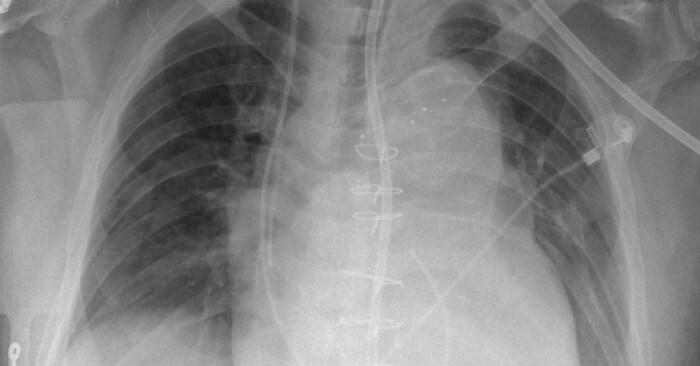

Attaching and de-attaching a grid in urgent care situations adds time and physical effort to the imaging process. This slows the path to diagnosis and increases the chance of error through potential issues like grid misalignment. Gridless X-ray capabilities provide a solution to this challenge, but come with their own set of complications such as an increased likelihood of scattered radiation that negatively impacts image quality.

SkyFlow gridless X-ray reduces the effect of scattered radiation for non-grid bedside chest exams, allowing for DR images with grid-like contrast while avoiding the time and effort of attaching and detaching a grid. SkyFlow identifies scatter signal and automatically applies correction immediately at the bedside, allowing radiologists to review images and make decisions on the spot.

With no grid to attach, SkyFlow scatter correction algorithm achieves the high-image contrasts that lead to a confident clinical diagnosis in emergency settings.